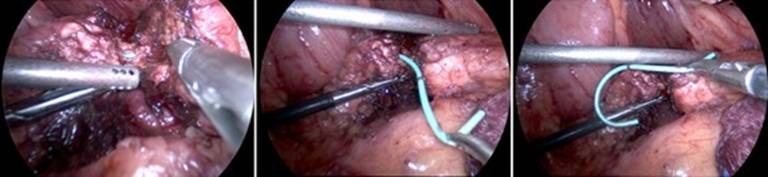

After accessing the abdomen through a supraumbilical Hasson approach, four additional trocars were placed in a semicircle around the head of the pancreas (three 5 mm and one 12 mm). The stomach was elevated off of the head, neck, and body of the pancreas. An intraoperative ultrasound was performed to find the distal aspect of the impacted stent. Once this was confirmed, the pancreas was circumferentially dissected free from the retroperitoneum and vasculature at this site. Then, using an ultrasonic dissecting device, the pancreas was slowly and methodically transected starting at the inferior border and proceeding from caudal to cranial. As the dissection proceeded, the pancreatic duct was then identified within the pancreatic parenchyma and transected with cold scissors. The pancreatic stent was identified (Figure 3) and removed without difficulty. The parenchyma proximal to this ductotomy site was transected with an endoscopic stapling device with staple line reinforcement using a slow compression technique. The pancreas to the left of the site of division was fully mobilized for approximately 3 cm and aligned to the posterior wall of the stomach. An anterior vertical gastrotomy was made, and a site was chosen for the posterior gastrotomy. A gastrotomy was made on the posterior wall of the stomach corresponding to the size of the distal remnant pancreas, and the pancreas was internalized into the stomach by pulling on the staple line. Then, the division of the partially transected pancreas at the level of the ductotomy was completed, resulting in a 2 cm segment of remnant pancreas invaginated into the stomach (Figure 4). An inner layer of running absorbable suture was used to create the pancreaticogastrostomy (Figure 5). An outer layer of running absorbable suture was placed from the nine o’clock to three o’clock position to further anchor the pancreas to the stomach (Figure 6). A 15F drain was placed in the region of the anastomosis. The patient tolerated the procedure very well, with a total operative time of 250 minutes, and recovered without any complications. The drain was found to have low volume and low amylase drainage on postoperative day six and was removed, and the patient was discharged. The patient noticed an immediate improvement in her epigastric pain, which continued to improve into follow-up.

Figure 3. Pancreatic ductotomy with exposure of the impacted 5 Fr pigtail pancreatic duct stent and subsequent removal with grasper and dissector devices. |